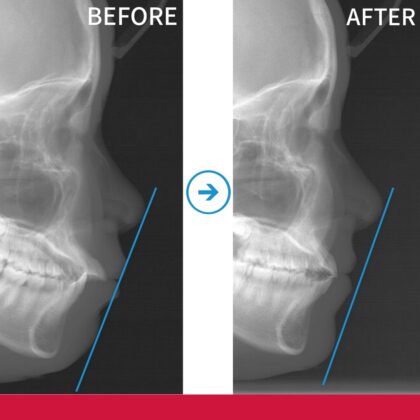

前歯が出ていることが気になる ▶

年齢 14歳 主訴 前歯が出ていることが気に...